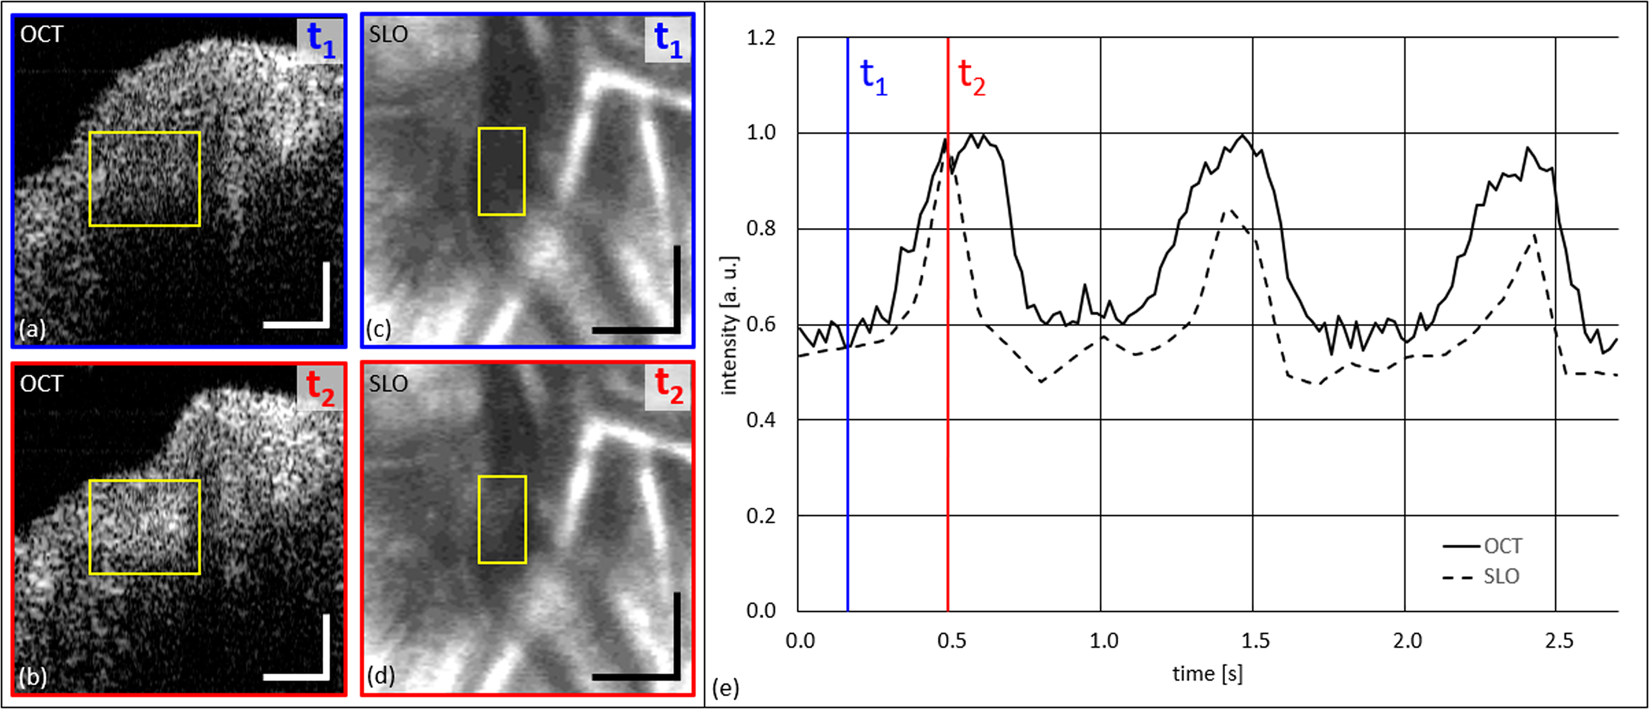

Investigation of pulsatile intensity changes at site of SRVP over three full cardiac cycles. (a,b) OCT tomograms at time points of t1 and t2. (c,d) SLO images at time points t1 and t2. (e) Graph of normalized (to maximum) change of intensity (OCT and SLO) within the yellow ROIs. Scale bars: (a,b): 0.1 mm; (c,d): 0.2 mm.